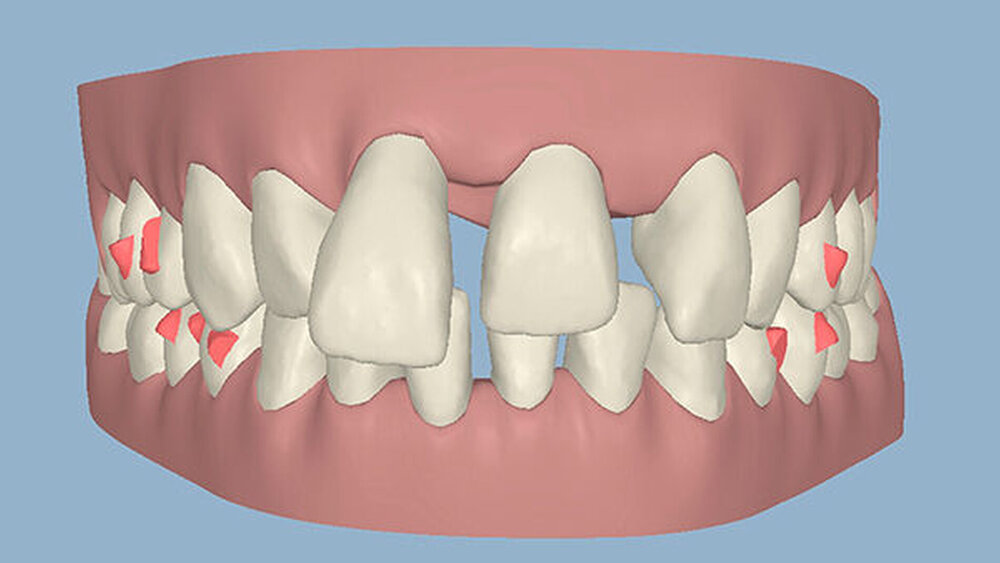

Um einen kompletten Lückenschluss im Oberkiefer zu ermöglichen, musste im Unterkieferfrontzahnbereich zusätzlich zur Derotation und Positionierung der Zähne - insbesondere Zahn 41 - von approximaler Schmelzreduktion, kurz ASR , Gebrauch gemacht werden, um einer Tonn`schen Diskrepanz entgegenzuwirken (Abbildung 4).

Die reine Intrusion von Zahn 11 konnte mit 2,5 mm beziffert werden, während Overjet und Overbite jeweils 2 mm und 3 mm betrugen (Abbildung 5). Die Abbildungen 6 bis 9 zeigen die Ergebnisse der Behandlung im zeitlichen Verlauf sowohl klinisch (Abbildungen 6 und 8) als auch in der bildgebenden Kontrolle (Abbildungen 7 und 9).